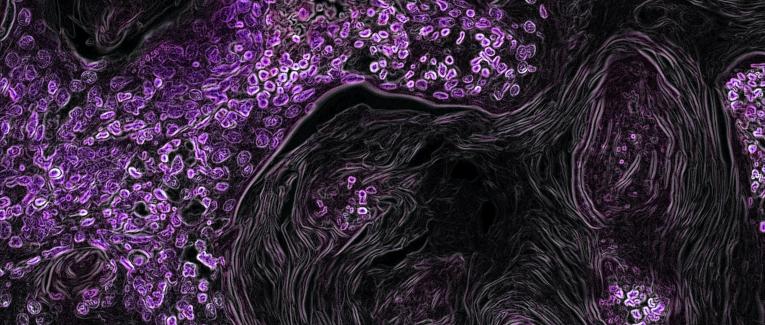

My pandemic story (crédits photo: National Cancer Institute) Notre secret: Un problème amusant auquel nous avons tous été confrontés! (crédits photos: Fayette Reynolds) Séparation: Famille et pandémie (crédits photo: M Shiva)